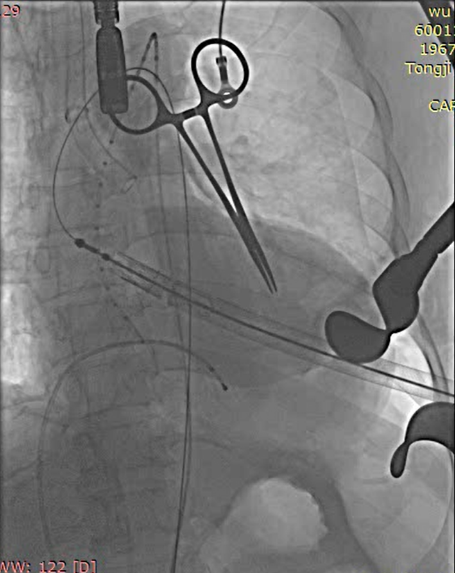

全麻后取仰卧位,消毒。取左前胸第5肋间切口进胸,腔镜辅助下游离左侧乳内动脉(LIMA)备用。肝素化。显露左前降支动脉(LAD),于其狭窄远段切开,将LIMA与之端侧吻合。血管桥排气后开放,测桥血流量满意。经股静脉植入心脏临时起搏器并确认正常工作。经股动脉置入造影导管至升主动脉根部,造影显示主动脉瓣大量反流,窦部结构可。3-0 Porlene线带毛毡片做荷包,经单弯导管引导超滑导丝至降主动脉,更换加硬导丝,导丝尖端于髂动脉分叉处。置入带主动脉瓣输送系统,造影定位下,准确释放29# J-Valve至主动脉瓣瓣环处,造影显示左右冠脉血流正常,TEE证实瓣膜位置可,未见明显反流。撤出输送系统,收紧荷包并缝合止血。放置胸管,逐层关闭各切口。

定位件入窦

瓣膜落座瓣环平面